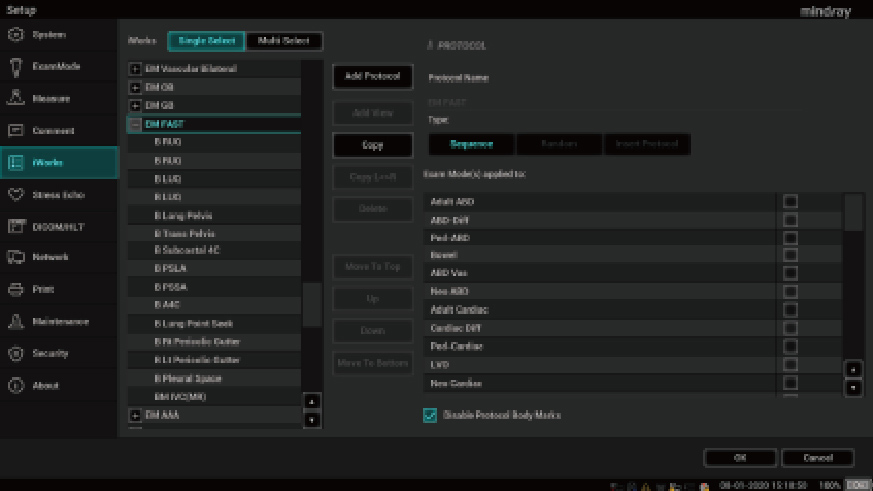

1Smart B-line

Automatically count the number of B-lines and percentage of area of B-lines according to the protocols. And score the performance of lung in four patterns according to lung aeration. Image overview and color map of score can assist on the assessment of pulmonary function.

2Smart VTI

Automatic measurement of the VTI (Velocity Time Integral) and CO (Cardiac Output), for rapid assessment of cardiac function. Automatically locate color box and PW sample line on real time. A graph of parameters trends about CO, SV and VTI to guide the decision-making.

3Smart IVC

Automatic measurement of IVC (Inferior Vena Cava) parameters, helps for volume status assessment and guides the fluid therapy. A graph of parameters change about CI or DI and IVCV for monitoring the change of critical ill patients.